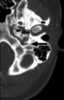

A congenital lip pit or lip sinus is a congenital disorder characterized by the presence of pits and possibly associated fistulas in the lips. They are often hereditary, and may occur alone or in association with cleft lip and palate, termed Van der Woude syndrome. [Source: Wikipedia ]